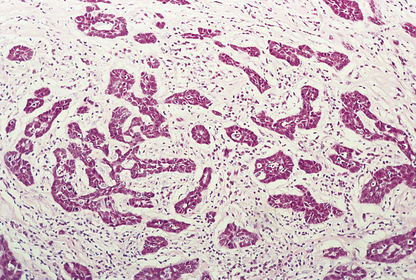

image

Fig. 18.3 A breast lobule showing the different components. The acinus is lined by epithelial cells surrounded by myoepithelial cells and the basement membrane.